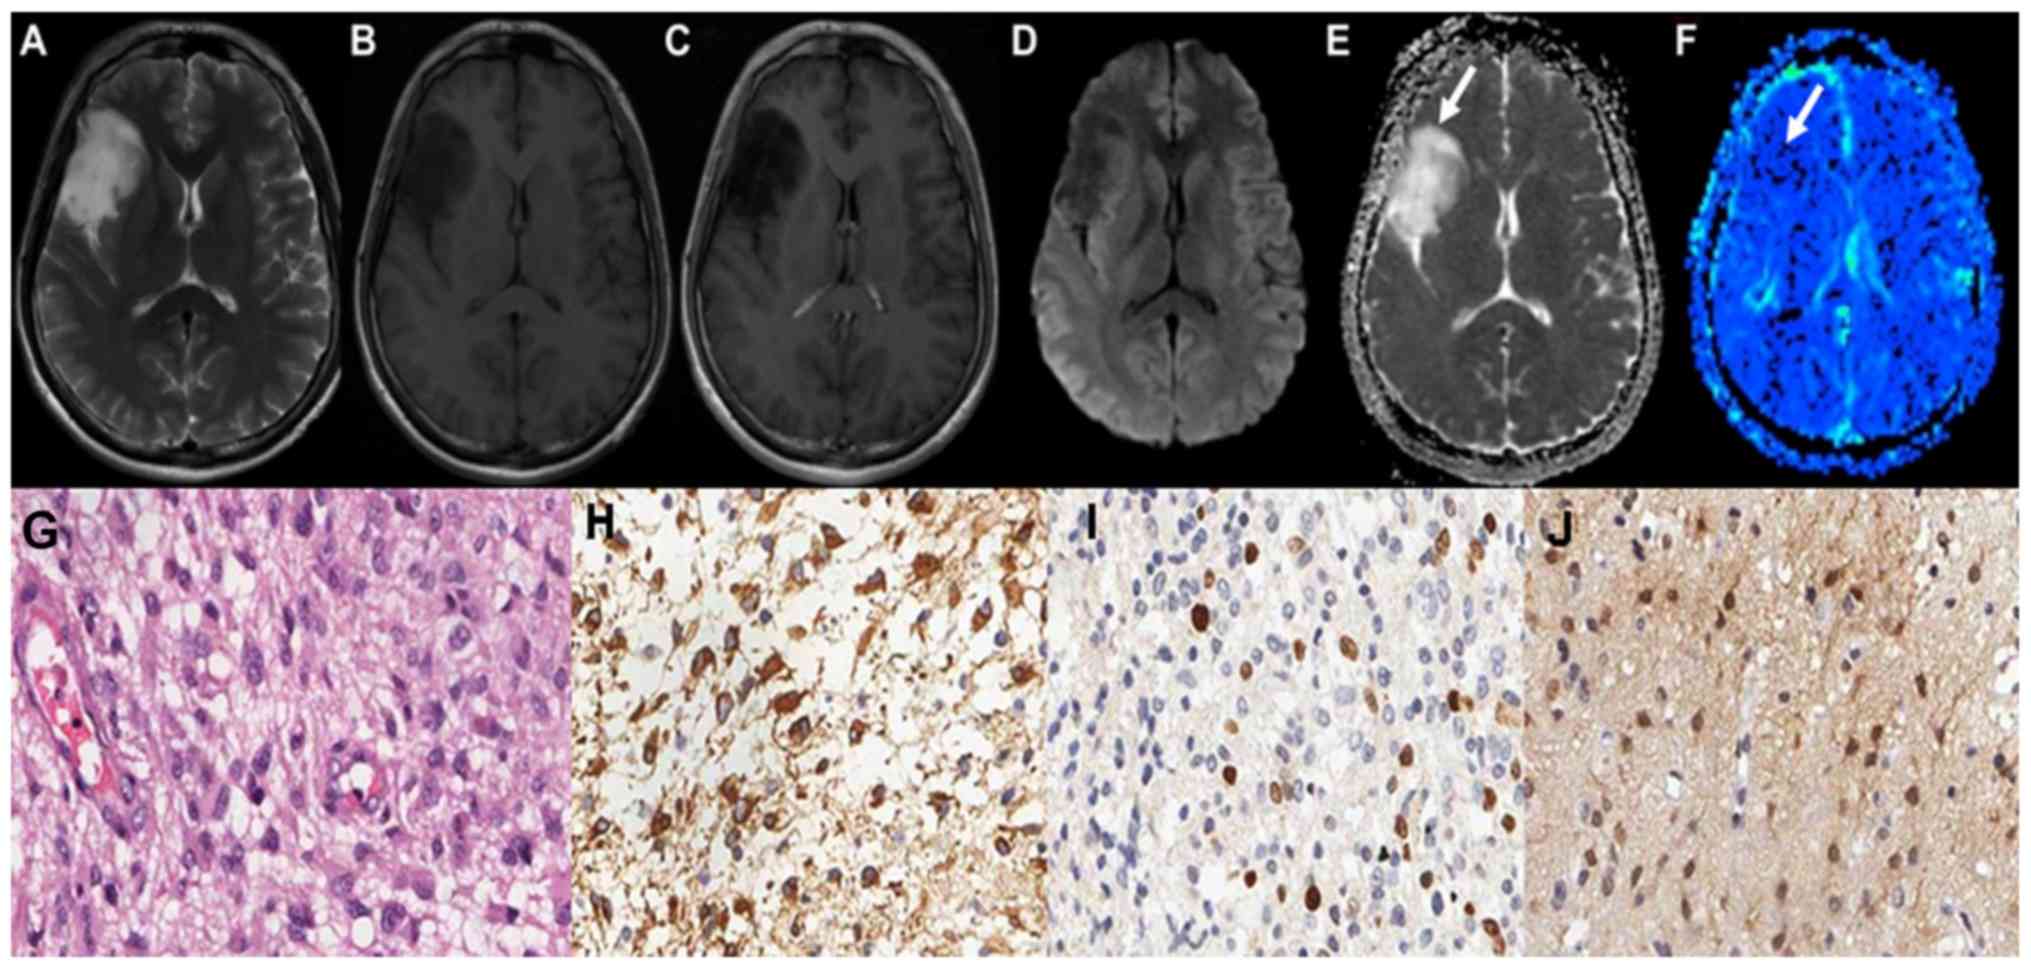

The maps of the aforementioned conventional MRI scans of grade II astrocytoma are demonstrated in Fig. 1A-C. Grade II astrocytoma exhibited low signal on DWI sequence, and high ADC values, as illustrated in Fig. 1D and E. The parenchyma of grades II astrocytoma on the rCBV maps exhibited low signals, as illustrated in Fig. 1F-J demonstrate the HE staining map, IHC. GFAP map, IHC. Topo IIα map and IHC. MGMT map of grades II astrocytoma respectively. The conventional MRI scans of grade III astrocytoma are demonstrated in Fig. 2A-C. Grade III astrocytoma demonstrated high signal on DWI sequence, and the ADC values of the tumor parenchyma were lower, as illustrated in Fig. 2D and E. The parenchyma of grades III astrocytoma on the rCBV maps exhibited high signals, as illustrated in Fig. 2F-J demonstrate the HE staining map, IHC. GFAP map, IHC. Topo IIα map and IHC. MGMT map of grades III astrocytoma respectively. The conventional MRI scans of grade IV astrocytoma are demonstrated in Fig. 3A-C. Grade IV astrocytoma demonstrated the highest signal on the DWI maps, and the ADC values were the lowest between all of the astrocytoma grades, as illustrated in Fig. 3D and E. The grade IV astrocytoma on the rCBV map demonstrated the highest signal, as illustrated in Fig. 3F-J demonstrate the HE staining map, IHC. GFAP map, IHC. Topo IIα map and IHC. MGMT map of grades IV astrocytoma respectively.

Figure 1.

Right frontal lobe low-grade astrocytoma (Grade II) in a 25-year old male. (A) The right frontal lobe lesion exhibited irregular long T1 and (B) T2 signals. (C) Axial contrast-enhanced T1 weighted image revealed no significant enhancement. (D) Lesions displayed iso-low signal on the diffusion-weighted imaging map. (E) The apparent diffusion coefficient map displayed high signal (arrow), (F) The relative cerebral blood volume value was low in the tumor parenchyma (arrow). (G) Well-differentiated tumor cells with slight nuclear atypia were exhibited on a hematoxylin and eosin staining map. (H) High expression of glial fibrillary acidic protein in the cytoplasm. (I) A limited level of expression of topoisomerase IIα in the nucleus. (J) The O 6-methylguanine-DNA methyltransferase proteins demonstrated moderate expression levels in the cytoplasm and nucleus.